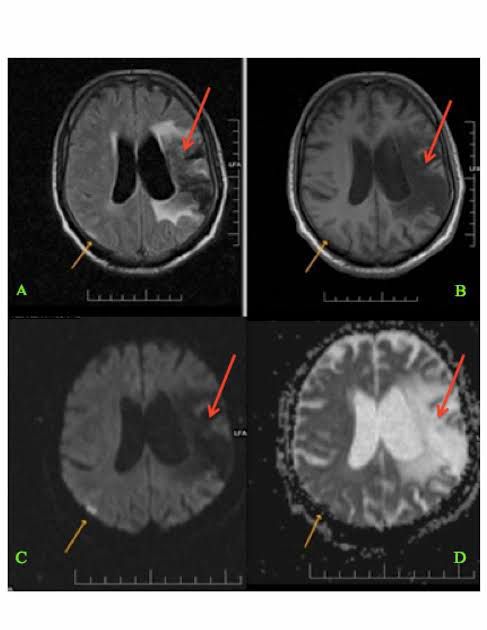

Hemiballismus is a hyperkinetic involuntary movement disorder characterized by intermittent, sudden, violent, involuntary, flinging, or ballistic high amplitude movements involving the ipsilateral arm and leg caused by dysfunction in the central nervous system of the contralateral side.